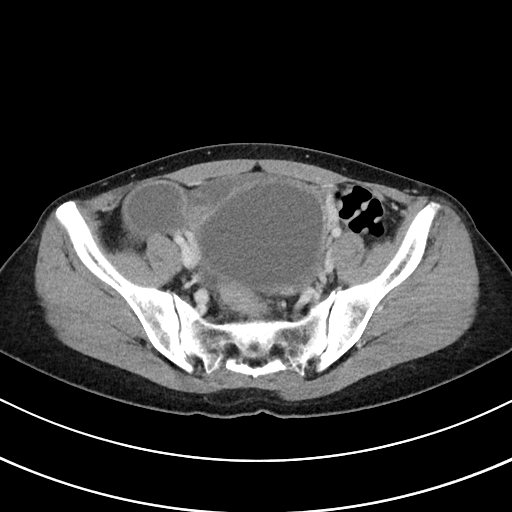

- 실제 예시

- CT 이미지(원천:PNG – 라벨링:JSON)

| 원천데이터 | 라벨링데이터 |

|---|---|

![]() |